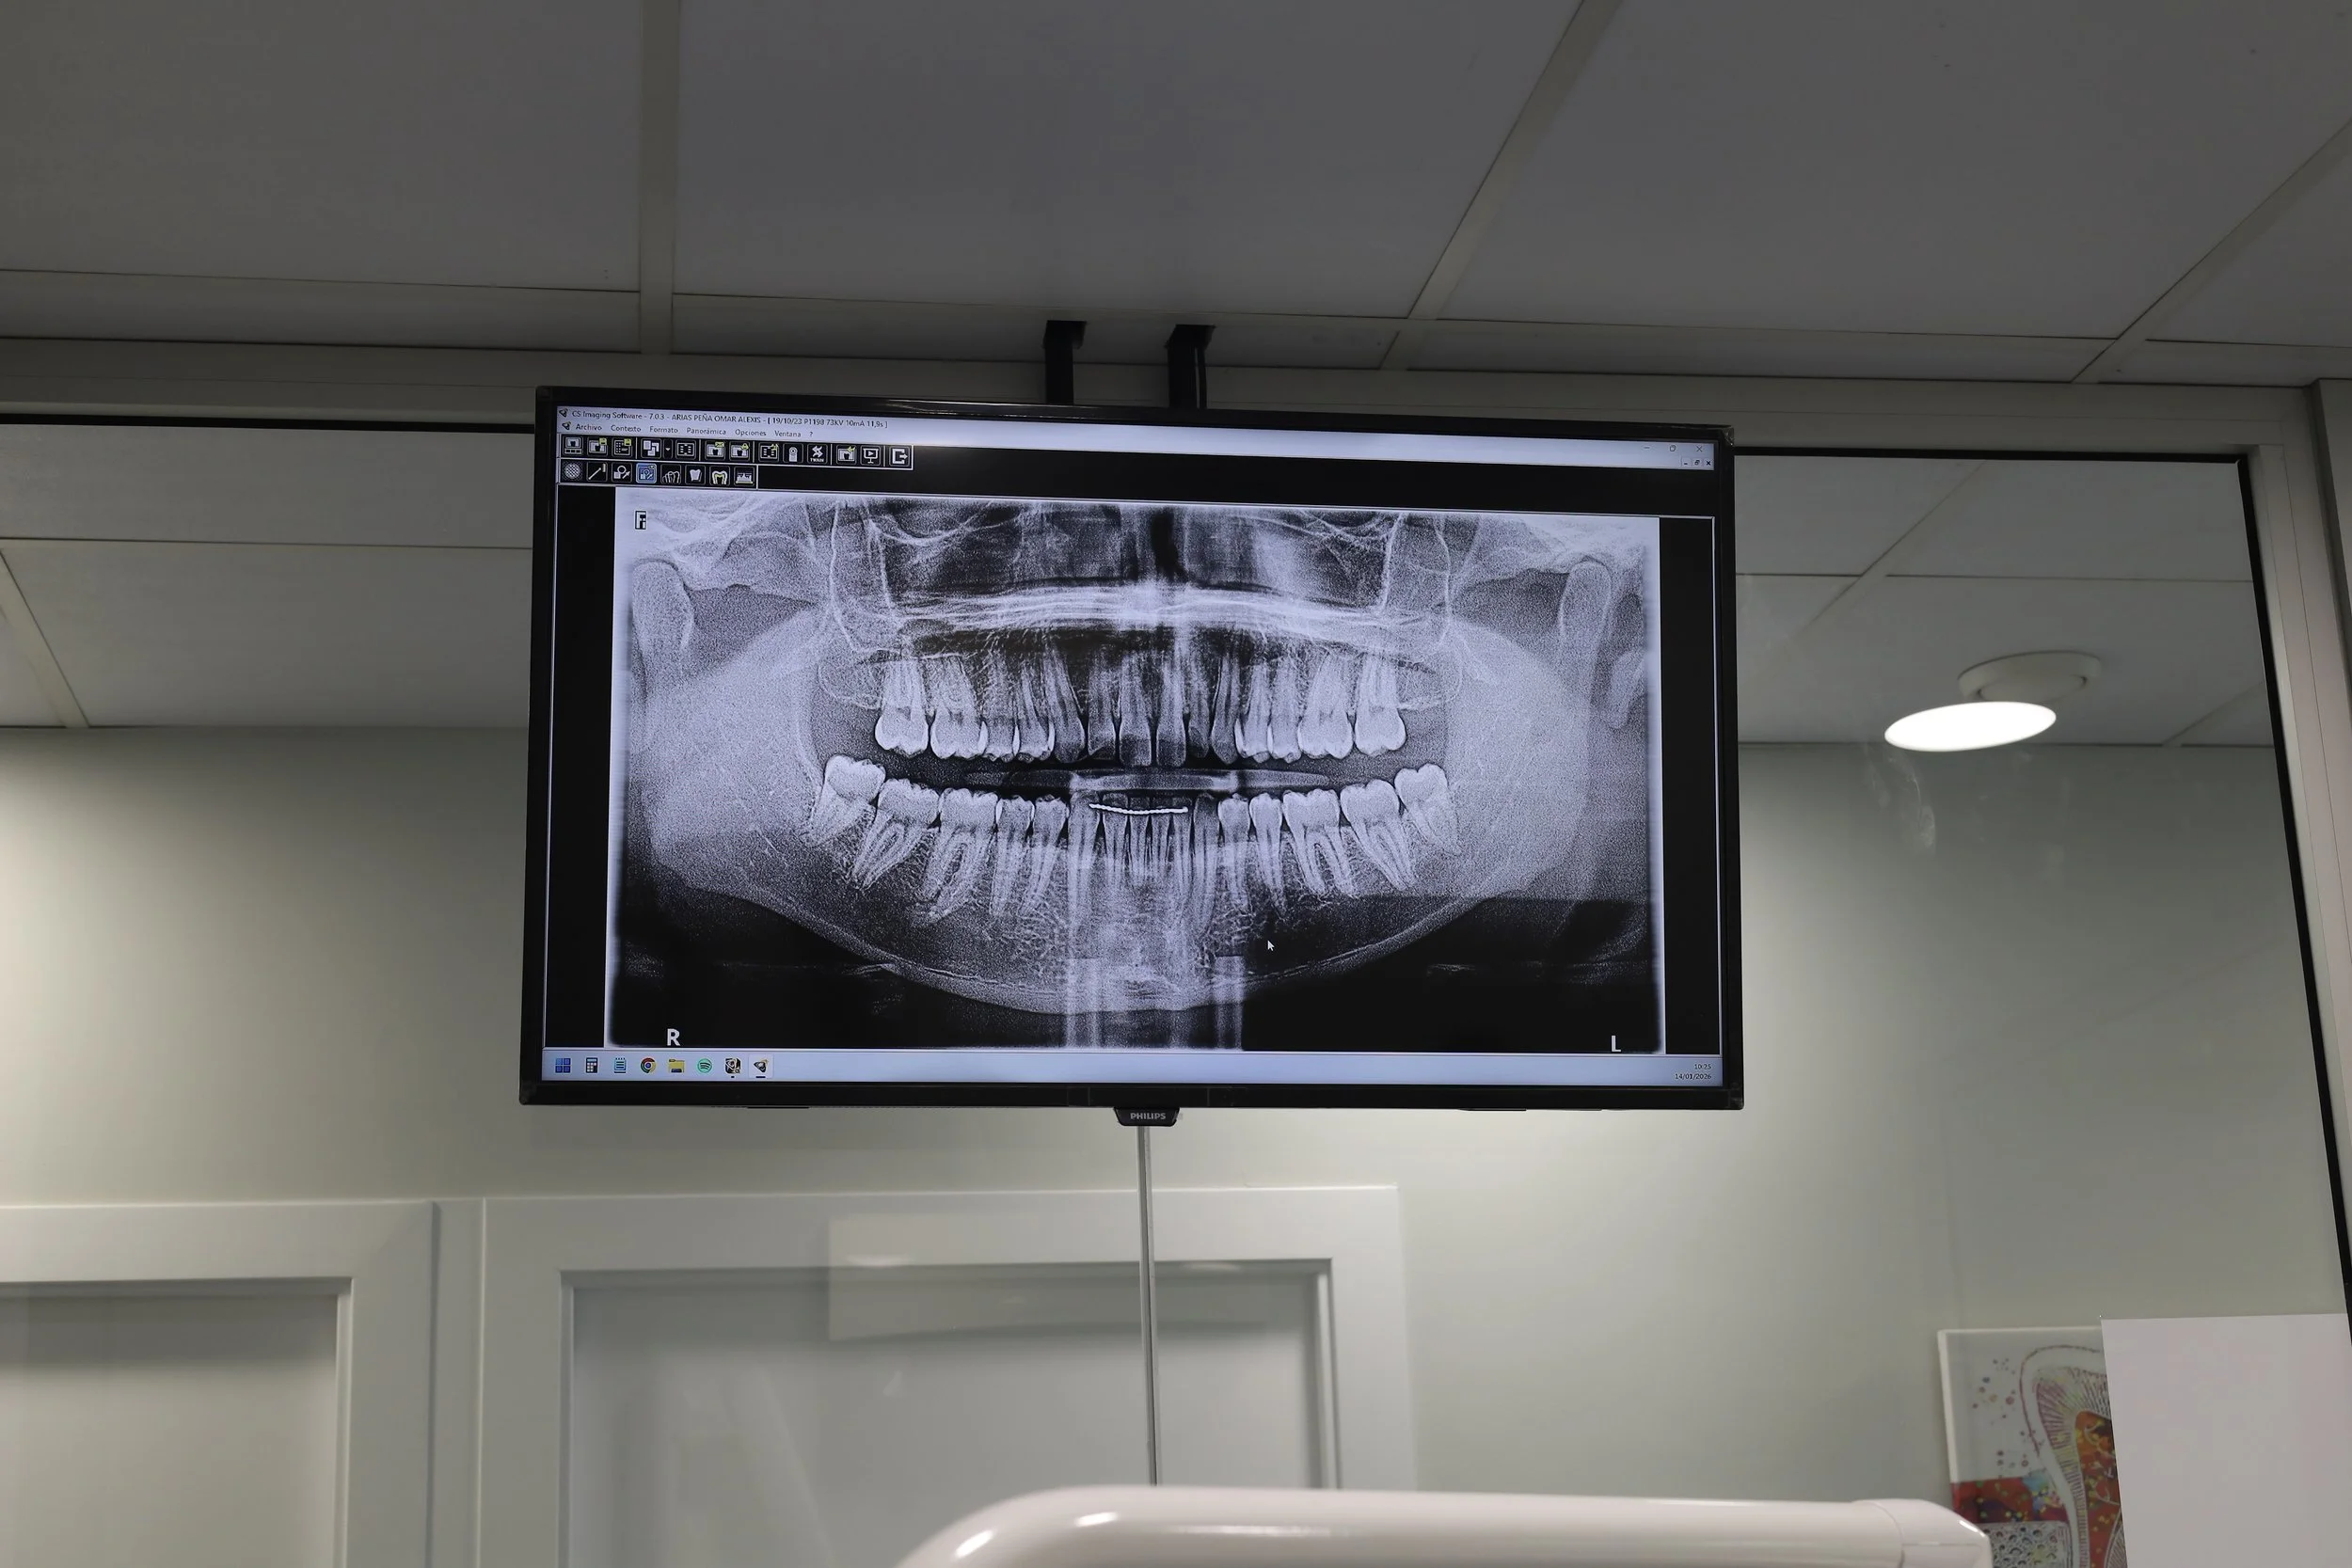

Estructura ósea:

Se tomarán radiografías para evaluar la calidad del hueso en su mandíbula superior e inferior y para determinar si se ha producido alguna pérdida de hueso.